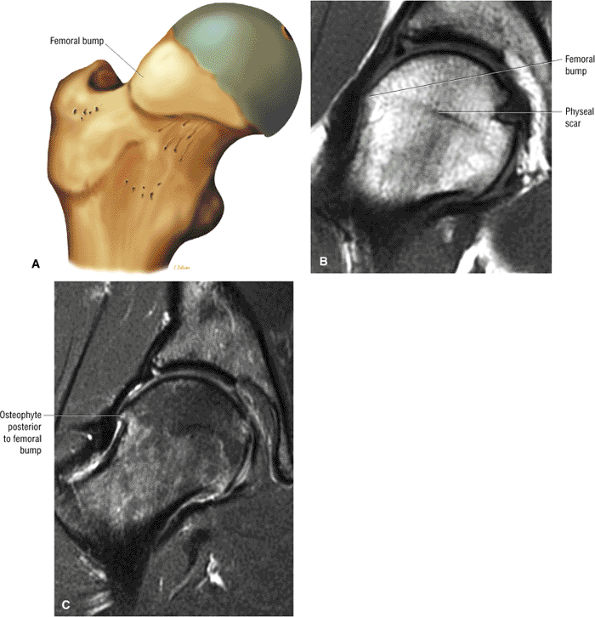

The femoral physeal scar is seen as a horizontal band of low signal intensity in an anterior-to-posterior orientation.

An enlarged or hypertrophied labrum may occur in patients with mild DDH.17 We have observed a femoral head chondral crease (Fig. 3.66) in these patients, creating a demarcation trough medial to a femoral head bump immediately proximal to the physeal scar. Patients who demonstrate femoroacetabular impingement (or lateral acetabular rim syndrome in DDH) also have direct impingement between the lateral acetabular labrum and the femoral head.